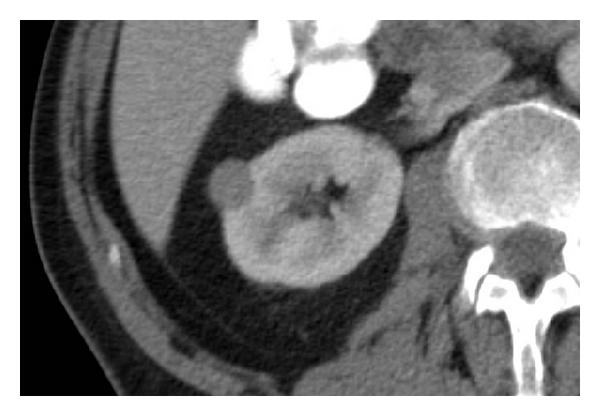

It is usually a hypodense mass, homogeneous, with smooth contours and a tendency to enhance avidly (see Figure 7). Until now, an oncocytoma was suggested on postcontrast CT by the presence of a central hypoenhancing scar. Because of its lack of specificity, patient management has been unaffected by the presence of this finding. Renal cell carcinoma and oncocytoma are indistinguishable from each other at imaging.